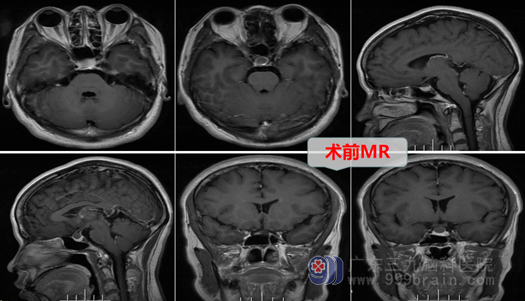

住院后,经过进一步检查,欧阳教授确定何女士患的病是:鞍区病变-鞍上型Rathke囊肿。Rathke囊是胚胎残余组织,位于颅底正中,大部分人出生后已经退化,但少数人残留并逐步长大、囊液越积越多,压迫脑垂体及视神经,引起多种临床症状。这种疾病以前治疗确实需要开颅手术,现在由于神经内镜技术的进步,更多的是采用更微创的内镜下经鼻蝶手术。Rathke囊肿多位于蝶鞍内,但何女士的囊肿却是位于鞍上。好在神经外十科在鞍区肿瘤手术方面有着非常丰富的经验,即使是这种鞍上Rathkena囊肿,也可以采取微创、经鼻-蝶手术,不用开颅。

欧阳辉教授带领外十科团队进行了认真的术前讨论,医生耐心详细地与何女士及其家属进行解释、谈话,终于解除了何女士心中的恐惧,她和丈夫都同意按医生的方案进行治疗。外十科团队在完善术前准备后,为何女士择期进行了内镜下经鼻蝶入路鞍上区Rather s囊肿切开引流术及大部分囊壁切除术。原来连打针都害怕的何女士在医生、护士鼓励下,硬着头皮进了手术室,医生耐心地安慰她,麻醉后,很快微创手术就做完了。手术很顺利,何女士得到了满意的治疗,术后回到病房,丈夫看见她头部连伤口没有,也没有纱布和绷带,更是非常高兴。现在她正一天天好转,很快就要恢复出院了。何女士感慨地说:微创手术真是太好了,人得了脑瘤,如果手术顺利,那么有一种感触:就是劫后重生,真要特别感谢外十科医生护士。